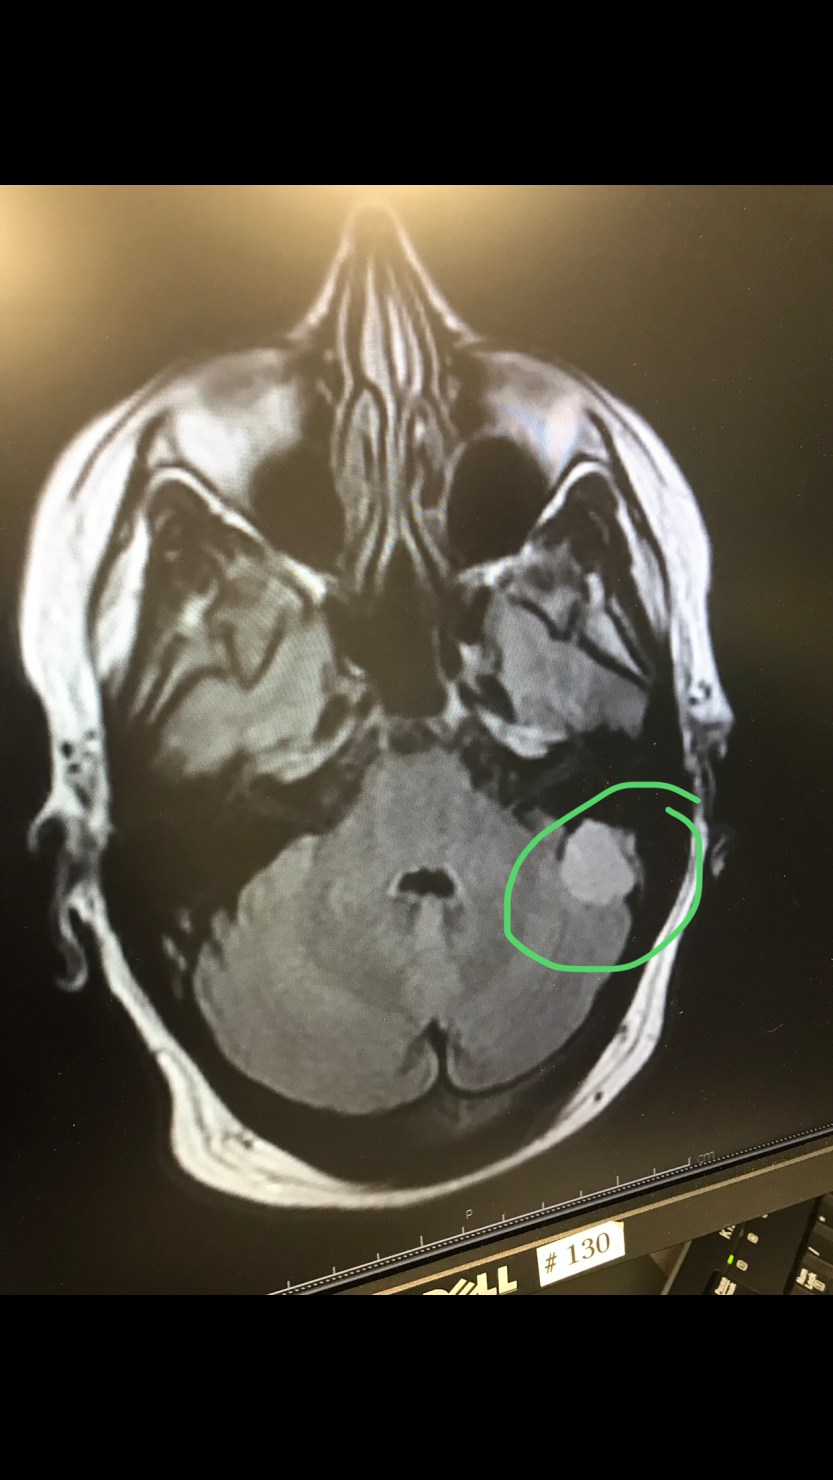

We were both wrong. I received a call from the neurologist himself that Monday morning saying that there was a tumor in my brain and the next step was to see a neurosurgeon. That was the only information given.

The doctor was calming from the moment he walked into the exam room. The tumor is benign. Non-cancerous. In an area that has few nerves that can be affected. Slow growing. Three options. First, wait to see what it does. Do an MRI every 6 months. Second, radiation. However, if the tumor grows 0.2 cm, radiation is no longer an option. Third, surgery. The decision is mine.

The size of the tumor is near a golf ball but shaped like an egg. Trying to keep a sense of humor, my family and I have named him George. Here he is in all of his glory. He is located behind my left ear.